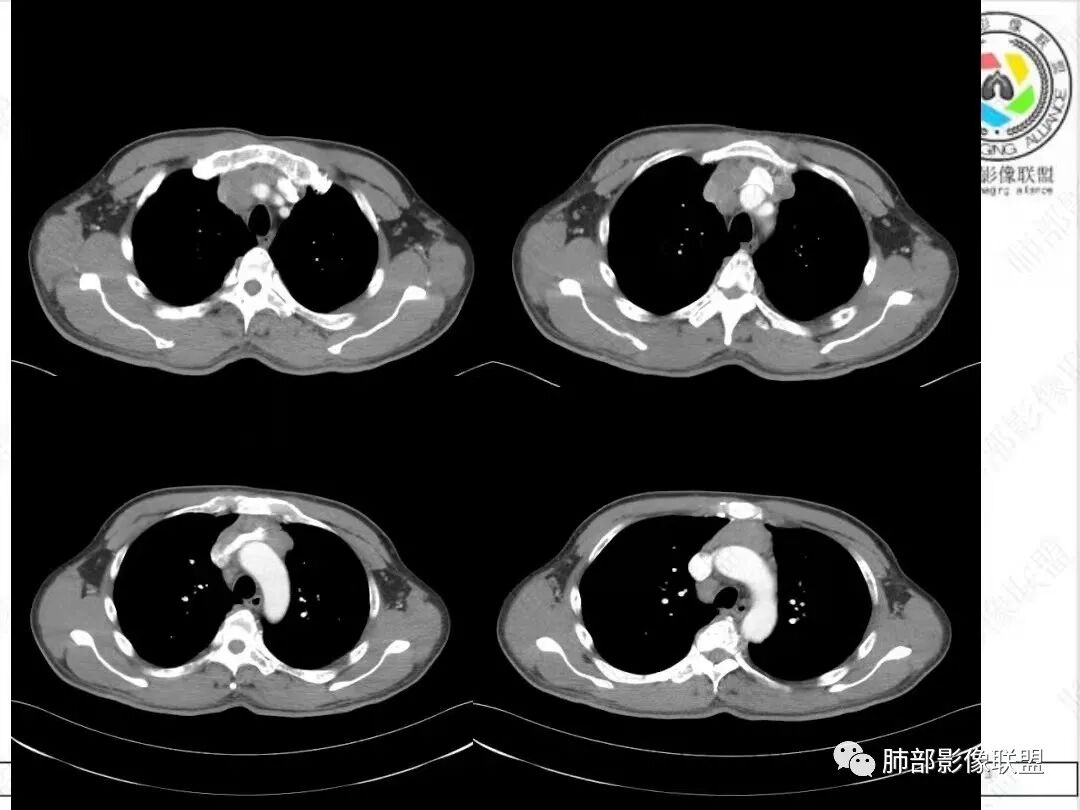

2、影像特点:胸部CT:平扫,前纵隔肿物,基本居中,与周围结构局部分界不清。增强后显示轻中度强化。肿块沿血管间隙侵袭性生长,左无名静脉受压明显变形受侵。纵隔、右肺门多处大小不等淋巴结,左侧内乳淋巴结稍增大。右侧瘤肺交界面光滑,左侧凹陷,肺组织未见明显受侵。右肺中下叶可疑小结节。胸椎及肋骨骨质增生性破坏。肋骨骨折。

病理结果:胸腺不典型类癌。

3、病例小结:  病人以胸痛就诊,无明显内分泌症状;前纵隔该部位肿瘤,胸腺瘤常见,乳酸脱氢酶偏高,55岁的年龄也较符合胸腺瘤,但胸腺瘤较少侵犯甚至包绕大血管生长、少有淋巴结肿大。

很多老师提到前纵隔占位+血管肿块内漂浮+内乳淋巴结增大+轻中度强化=淋巴瘤,淋巴瘤确有上述特点,但本例血管漂浮不明确,病灶强化不均匀,胸椎及肋骨可疑增生性转移,应想到胸腺癌或不典型类癌的可能性。